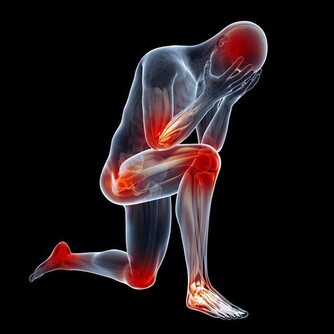

糖尿病是一種慢性進行性疾病,患者不是不能有更長的壽命,但這要求他們必須花更多時間來對付並發症。並不是說所有糖尿病患者都注定會出現並發症,而是說,你必須防止問題出現。

長期高血糖會對身體的許多器官造成傷害,但積極改變生活方式有助於降低血糖和預防糖尿病並發症。採取行動永遠不會太晚,即使你已經患有糖尿病很多年,仍然可以做出改變以改善健康狀況。